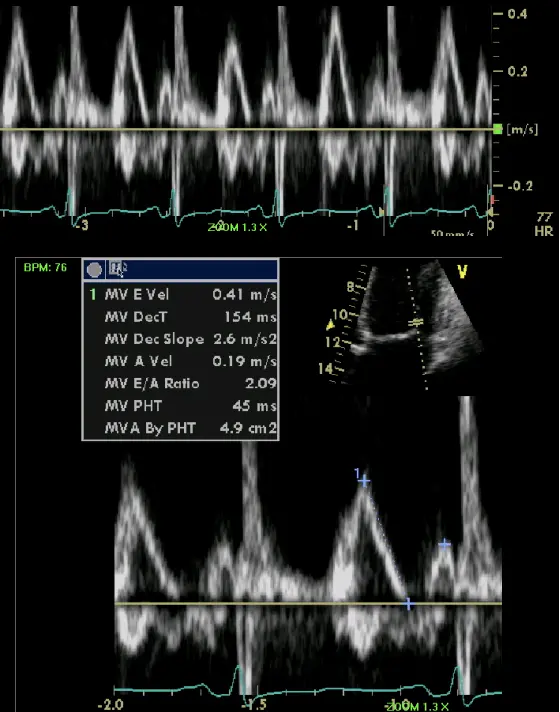

- Specific diagnostic echocardiographic criteria for the diagnosis of constrictive pericarditis has been proposed by the Mayo Clinic and include:

- septal bounce or ventricular septal shift with either medial e′ >8 cm/s or hepatic vein expiratory diastolic reversal ratio >0.78 (sensitivity 87%, specificity 91%; specificity may increase to 97% if all criteria are present with a correspondent decrease of sensitivity to 64%

- Combined parameters from mitral inflow, mitral annular velocities, and hepatic vein velocities have made the diagnosis of constriction and its differentiation from myocardial disease much easier than ever before.3

- Three variables were independently associated with constrictive pericarditis: 1) the presence of ventricular septal shift, 2) medial mitral e’ velocity; and 3) the hepatic vein expiratory diastolic reversal ratio. 2

- The presence of ventricular septal shift in combination with either medial e’ ≥ 9 cm/s or hepatic vein expiratory diastolic reversal ratio ≥ 0.79 (Hepatic vein diastolic reversal velocity / diastolic forward flow velocity) was 87% sensitive and 91% specific for the diagnosis of constrictive pericarditis.

- Ventricular interdepence and Respirophasic Variation

- Expiration: mitral inflows ↑, tricuspid inflows ↓

- Mitral inflow ↑ respiratory variation, ↑ E/A, ↓ E deceleration time